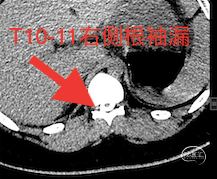

患儿仅15岁,因长期受此病困扰,沟通之后很快接受了脊髓造影,如下图:

明确瘘口之后,接受了T10-11靶向血贴治疗。